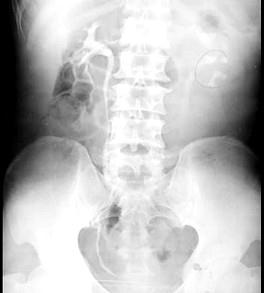

问题 关于肾结核药物治疗正确的有 ( )

选项 A、最好用三种药物联合 B、轻者5年不复发即可认为治愈 C、药量要充分、疗程要够长 D、治疗中应每月检查尿常规和尿结核杆菌 E、连续一年尿中未找见结核杆菌称为稳定阴转

答案 ABCD